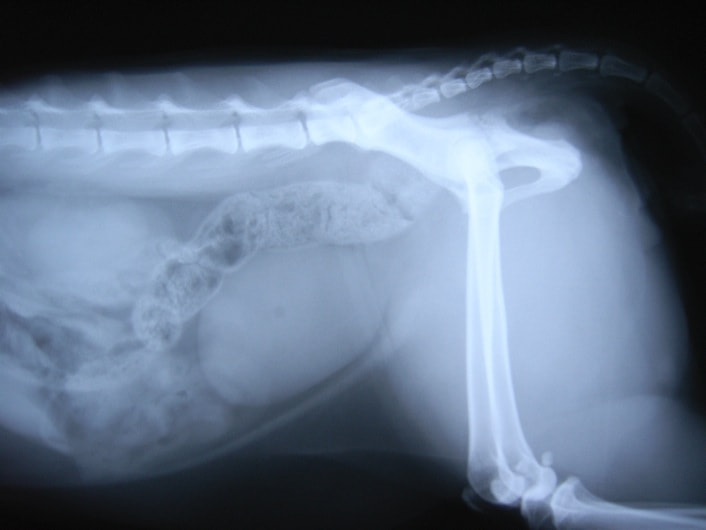

症例:交通事故による椎体脱臼

柴犬:9歳、避妊雌

交通事故直後、胸腰部に激しい疼痛、両後肢に完全麻痺を認め、シェフシェリントン徴候を呈していました。レントゲン検査において、第11-12胸椎間の脱臼が認められました。

脊髄の減圧、脊柱管の再構築・安定化を目的に、片側椎弓切除術およびMatrixMANDIBLE Plateによる椎体固定を実施しました。

隣接椎体を架橋するようにプレートを設置しました。

術後レントゲン写真